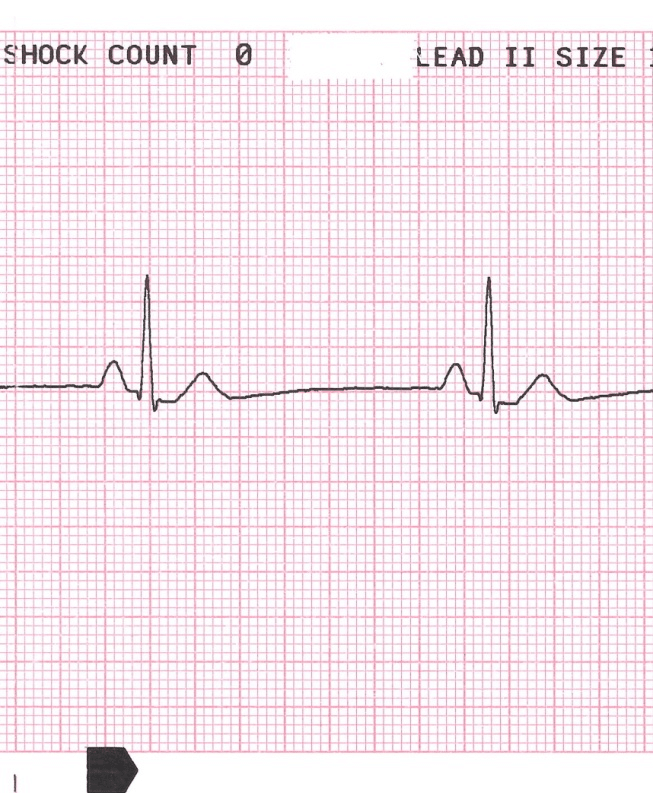

- Bradicardia sinusal com FC <50 bpm

- Síndrome bradi-taqui: A taquicardia atrial (geralmente FA) é que mais comumente é seguida por uma pausa sinusal no final da taquicardia. Essa transição geralmente leva a síncope ou pré-síncope.

- O QRS é estreito ou largo? O bloqueio AV com um QRS estreito geralmente indica que o bloqueio está no nó AV e que conduz através do sistema His-Purkinje normalmente. Portanto, a atropina ajudará. Se o bloqueio AV é infra-nodal, a atropina não ajuda e tem relatos de que piora os atrasos de condução. Opte por uma catecolamina (ou simplesmente ponha marcapasso) a menos que haja preocupação com uma possível isquemia miocárdica como causa da bradicardia.